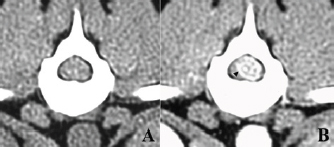

An 18-month-old spayed female crossbreed dog presented with progressive hindlimb paralysis over the previous months. She could not stand or walk unaided at her first visit and showed severe pain upon palpation of the thoracolumbar spine. Plain spinal radiography and routine blood tests were normal. Computed tomography of the thoracolumbar spine showed a clear contrast-enhanced mass lesion of the spinal cord at T13, suggesting the presence of spinal tumors; however, the detailed relationship between the tumor tissue and the normal spinal cord was unknown (Fig. 1). Six days later, the dog underwent surgical removal of the presumed tumor under general anesthesia, as the animal’s owner wanted aggressive treatment, including surgery.

Fig. 1. Computed tomographic findings at T13 of the case. (A) Without contrast medium, (B) with an intravenous administration of contrast medium. A clear contrast-enhanced mass lesion of the spinal cord could be observed in the contrast study (B, arrow head).